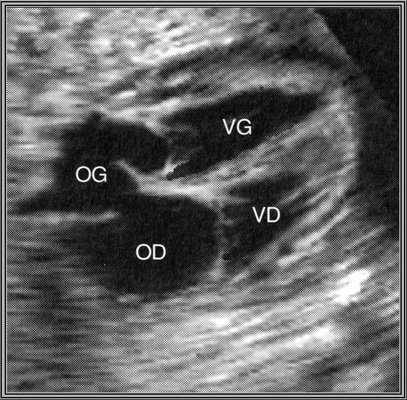

Dextrocardie

4 cavités